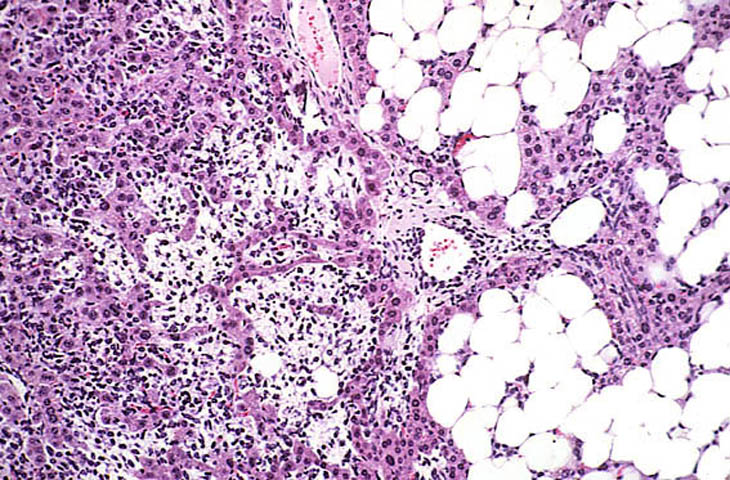

A relative discrete Ito cell tumor is present within this hepatic lobe; a higher magnification shows proliferation of stellate cells within the hepatic sinusoidal spaces.